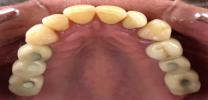

If multiple teeth are missing in different parts of the mouth, several single tooth implants are excellent replacement restorations. Multiple tooth implants provide a firm base to the spaces of the missing tooth inside the patient’s mouth. In individuals who have multiple missing teeth in their mouth, replacement of those missing teeth areas becomes crucial. Starting with the dental implants treatment without any delay is important. Fixed bridges can be placed efficiently with the help of the multiple tooth implants successfully in the recent times. The success rate of the multiple tooth implants if different types of cases are worth appreciating. It also helps the patients to eat the foodstuffs they want just within few days of the successful completion of the placement of the multiple teeth implants.

The best part is that multiple tooth implants are placed individually at each of the missing teeth locations. Therefore, the implants do not interfere with the functioning of each other, thus providing a firm base and support to the adjacent and opposite teeth too. Also, the alveolar bone which holds the tooth is prevented from deteriorating with the help of the placement of the multiple teeth implants at the irrespective locations. The best part is that you need not worry regarding the resorption of the alveolar bone associated with the missing teeth which usually occurs in the absence of natural teeth or dental implants.

If more than one teeth are missing within the same region in the patient’s mouth, then space can be successfully replaced with multiple tooth implants. So, you can see that you can get better and stronger support for your alveolar bone and surrounding tooth structures in the mouth with the help of the multiple tooth implants. This solution includes having implant fixed bridges done. Patients can apply normal forces while chewing like the same as that of the natural tooth. Also, you can ensure that there is no displacement of the dental implants in most of the patients until a decade or so. In this way, you can entirely trust on the multiple teeth implants for the replacement in the missing teeth area in your mouth. One of the major features is that after the placement of the dental implants, dental crowns are fixed on them thus providing a natural yet aesthetic appearance to your smile for the rest of your life.

We use only top end dental Implants – Nobel Biocare from Sweden & Straumann from Switzerland.